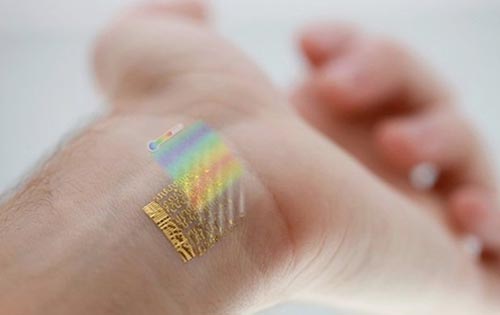

Σχεδόν αόρατοι αισθητήρες καταγράφουν βιομετρικά δεδομένα Την ίδια ώρα που αρκετοί άνθρωποι αρχίζουν να εντάσσουν τη γυμναστική και την ευεξία στην καθημερινότητά τους, οι επιστήμονες εργάζονται σκληρά προκειμένου να κατασκευάσουν ολοένα και πιο μικρούς, αλλά εξειδικευμένους αισθητήρες. Αυτοί οι μηχανισμοί είναι σχεδιασμένοι έτσι ώστε να εφαρμόζουν επάνω στα σώματα των …